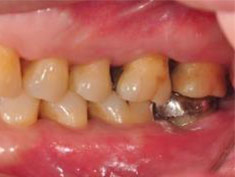

牙周初診時患者之口內觀。口內明顯牙菌斑及牙結石堆積。全口嚴重牙齦紅腫。治療前X光片。#37的近心側有較深的骨內缺損,剩餘齒槽骨高度只有20%。

第一階段牙周基本治療後,牙齦發炎狀況明顯獲得改善。